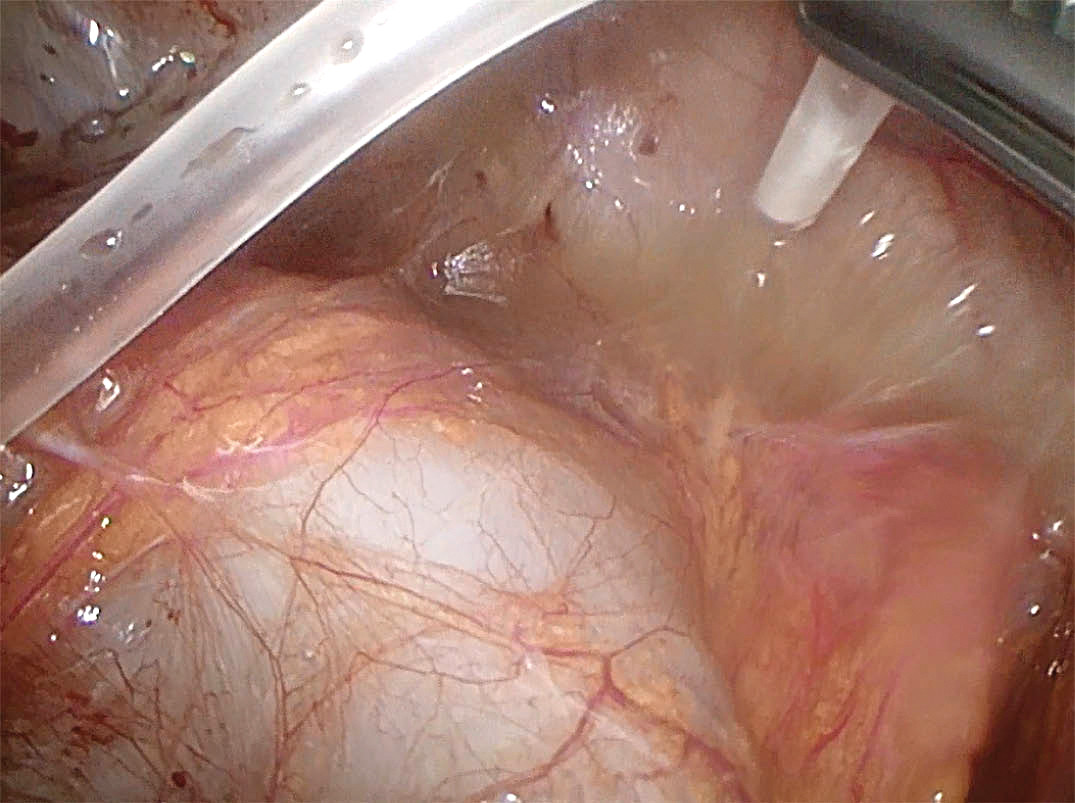

Initialt observerte man klinisk og biokjemisk respons etter transvaginal tapping, men pasienten fikk på nytt febertopper opp mot 39 °C og stigende infeksjonsprøver etter fem dager. Mikrobiologiske prøver fra ovariet var negative. Seks dager etter tappingen gjorde man diagnostisk laparoskopi og fant en inflammert og totaladherent buk samt rikelige mengder puss i bekkenet (figur 3 og 4). Det ble gjort omfattende adheranseløsning og skylling. Nye mikrobiologiske prøver ble tatt. Denne gangen ble det sendt inn rikelig mengde puss på sterilt glass.